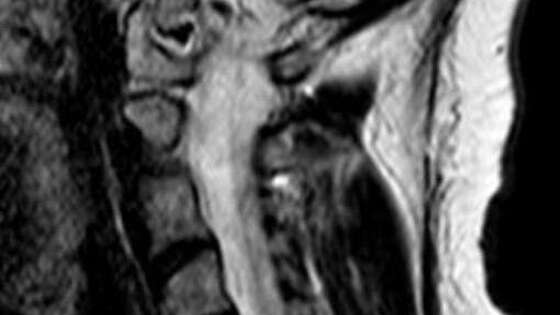

Врачи Истринской больницы спасли от паралича руки 37-летнюю женщину, у которой в шейном отделе нашли грыжу. Об этом сообщили в пресс-службе минздрава Московской области. Пациентка обратилась с жлобами на изматывающую боль в руке. Ей провели МРТ, которое показало, что в шейном отделе сформировалась грыжа размером 8 мм. По словам медиков, образование сдавливало спинномозговой канал и корешковое отверстие, угрожая двигательной функции. "Мы провели сложнейшее микрохирургическое вмешательство, в ходе которого удалили грыжу и стабилизировали позвоночник с помощью современного импланта", - рассказал нейрохирург Николай Карпов, отметив, что операция длилась два часа 20 минут. На пятые сутки женщину выписали на амбулаторное лечение. Она идет на поправку.